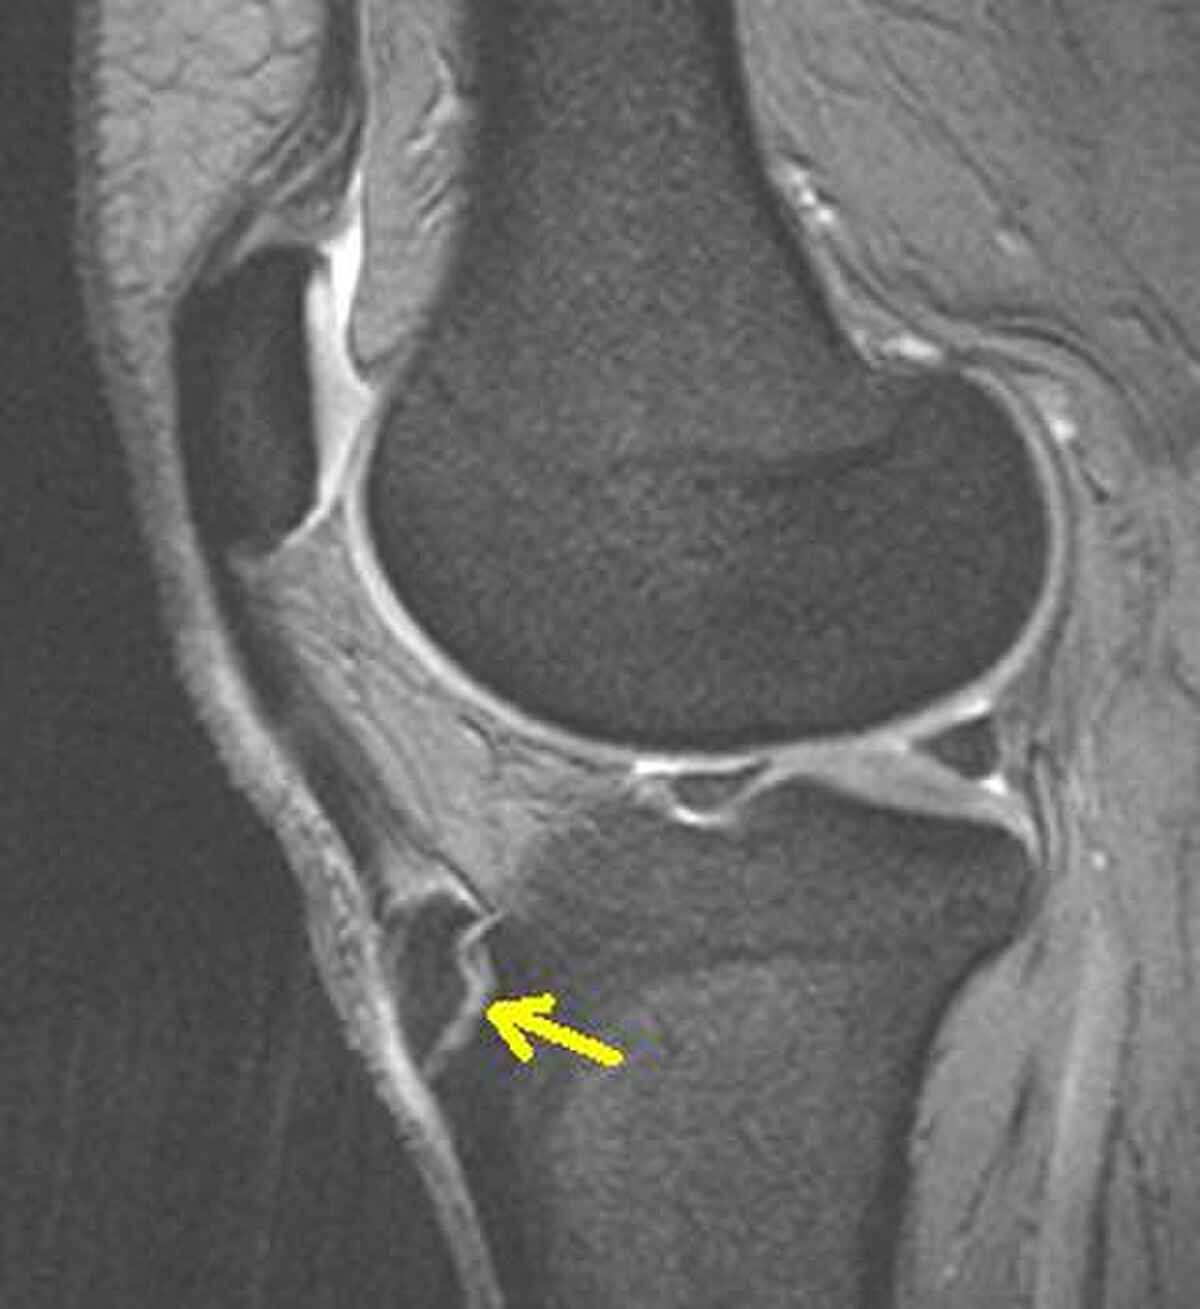

Une radiographie n'est pas nécessaire notamment lorsque le tableau clinique est évocateur et que les douleurs sont bilatérales. Elle peut être utile pour éliminer une autre pathologie si les douleurs sont unilatérales, atypiques ou rebelles au traitement. Initialement on retrouve un soulèvement de la tubérosité tibiale antérieure avec élargissement de son cartilage de croissance; dans les stades plus évolués, la TTA est fragmentée et on peut voir parfois des calcifications dans le ligament rotulien.